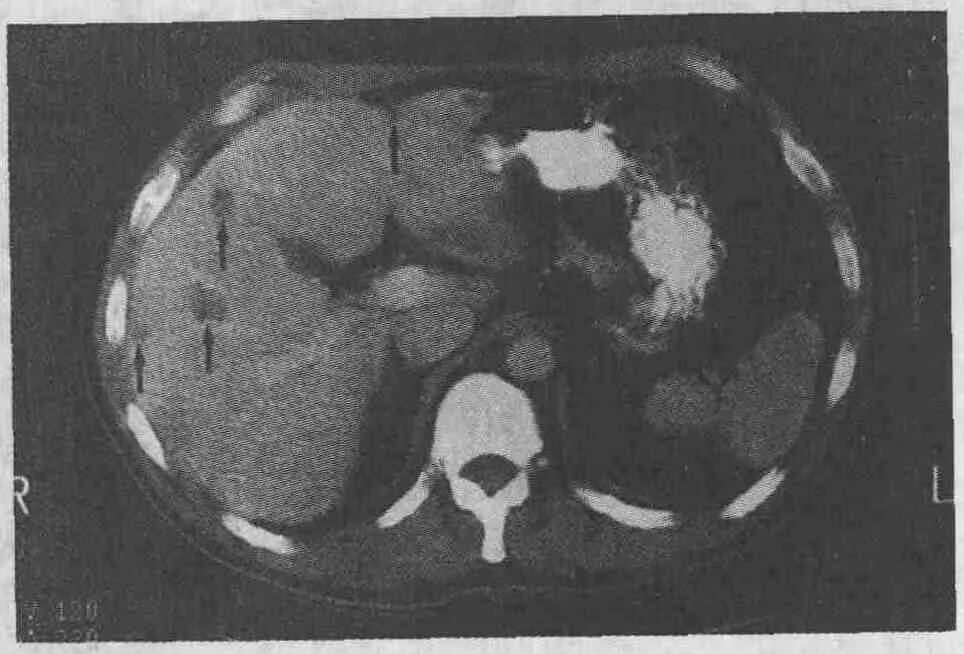

Цирроз на кт